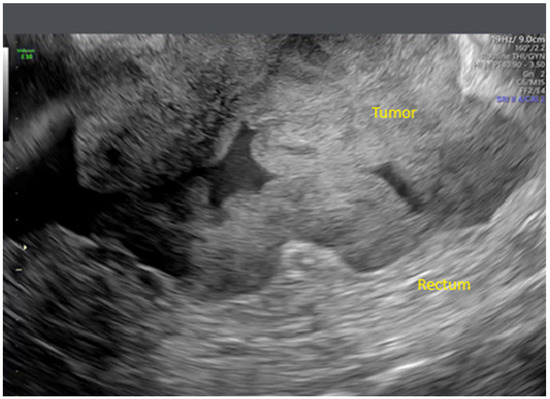

Background: Ovarian cancer is one of the most lethal gynecological malignancies, often diagnosed at an advanced stage. The prognosis is generally poor, with high recurrence rates and limited long-term survival. Understanding the genetic and molecular...